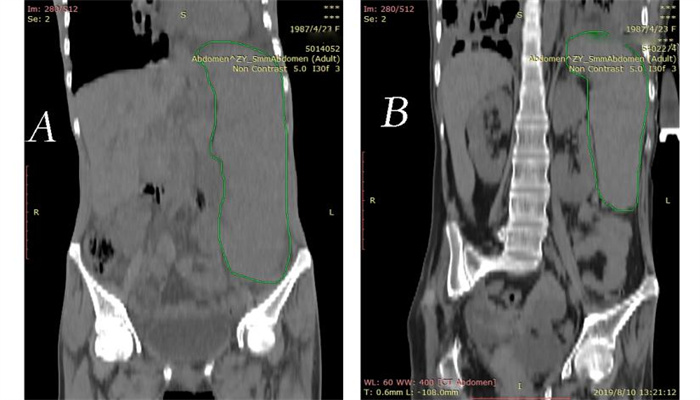

| A:患者入院肺部CT,提示双肺支气管扩张并感染,左肺部分不张;B:患者出院肺部CT,提示支气管扩张 图 1 患者肺部CT图像 |

患者女,31岁,因“咳嗽、咳痰伴腹胀3 d”于2019年2月4日转诊至遵义医科大学附属医院。入院前3 d,患者咳嗽、咳痰,发热39℃,伴腹胀、腹痛,就诊当地医院,考虑“肺部感染、脾大”,予抗感染治疗,无好转遂转院。患者既往史、个人史及流行病学史无特殊。查体:呼吸34次/min,体温39 ℃。双肺闻及湿性啰音,左腹部及脐周压痛,肋缘下10 cm触及脾脏,越过前正中线。胸部CT示支气管扩张并双肺感染,腹部CT示巨脾,体积1 755.064 mm3。白细胞(WBC)2.24×109/L,红细胞(RBC)2.71×1012/L,血小板(PLT)67×109/L,C反应蛋白(CRP)73.60 mg/L。入院诊断:(1)脓毒症、支气管扩张并感染;(2)三系(WBC、RBC、PLT)减少,原因:脾功能亢进;(3)巨脾。诊断依据:(1)患者临床表现及病史;(2)检查、检验结果;(3)sepsis 3.0,SOFA评分大于2分;(4)结核检测及胸部CT排除结核分枝杆菌感染,骨髓穿刺结果不支持血液及淋巴系统疾病,回顾患者既往病史及腹部CT图像排除肝硬化等疾病。多学科会诊:针对巨脾,考虑脓毒症所致充血性肿大,不考虑肝硬化及班替氏综合征,继续抗感染治疗, 菌培养+药敏结果提示哌拉西林舒巴坦钠、盐酸莫西沙星敏感的金黄色葡萄球菌,最终诊断:(1)脓毒症;(2)支气管扩张并感染;(3)巨脾;三系减少病因:脾功能亢进。再次根据药敏试验调整抗生素,患者体温恢复正常,脾脏体积出院时仅有641.545 mm3, 三系终于恢复正常范围,感染指标下降,好转出院。